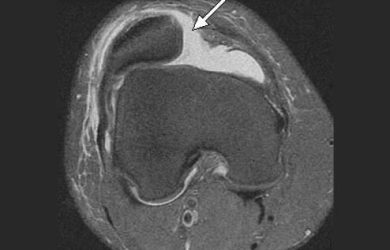

Хвороба Кеніга (розсікаючий остеохондрит колінного суглоба) – досить рідкісне захворювання, при якому розвивається обмежений остеонекроз ділянки субхондральної кістки,